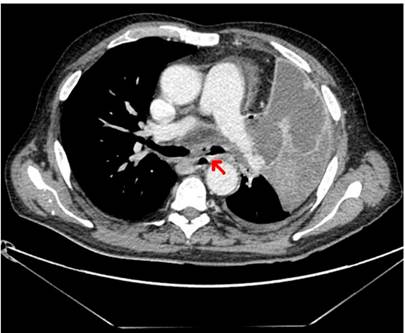

Se realizó una endoscopia digestiva alta (EDA) en la que se observó una lesión esofágica amarillenta y blanquecina de 0,8 cm en torno a los 29 centímetros de la arcada dental, que no aparentaba originarse en la mucosa esofágica ya que presentaba un movimiento independiente (Figura 1) y que sugería la presencia de una fístula esofágica. Se realizó una tomografía axial computarizada (TAC) que confirmó el diagnóstico de fístula broncoesofágica asociada con una masa mediastínica (Figura 2). Una broncoscopia posterior mostró una masa endobronquial obliterante y necrótica, con pseudomembranas de aspecto maligno.

Figura 2 Imagen de TAC que muestra la comunicación entre el esófago y el bronquio asociada con una masa mediastínica.